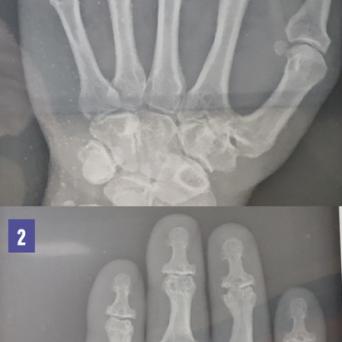

L’image

du jour